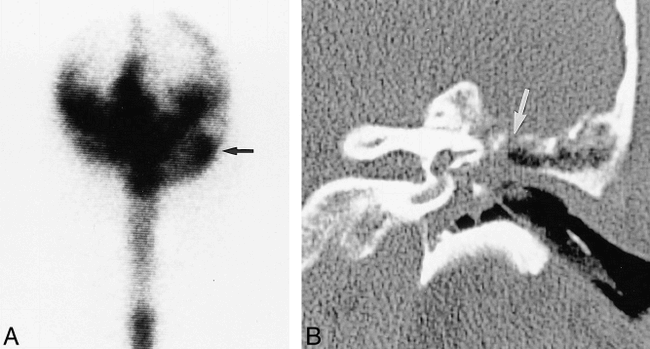

Patient with a bone defect revealed by CT and positive results of radionuclide cisternography and CT cisternography.

A, Coronal CT scan of the face shows a defect (arrow) of the lateral sphenoidal sinus roof with mucosal thickening filling the sphenoidal sinus.

B, Coronal contrast-enhanced CT cisternogram shows contrast medium extending through the defect (arrow) and within the right sphenoidal sinus (curved arrow). The nasal pledgets indicated a leak in the region of the right sphenoethmoidal recess, although the cisternogram did not show abnormal accumulation of the radionuclide. The defect and CSF leak were confirmed at surgery.